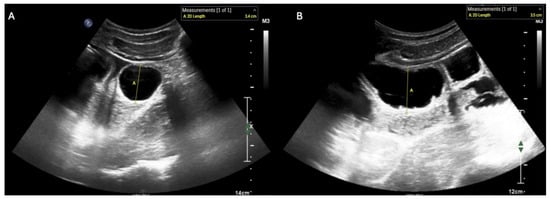

- Ogata, M.; Imai, S.; Hosotani, R.; Aoyama, H.; Hayashi, M.; Ishikawa, T. Abdominal sonography for the diagnosis of large bowel obstruction. Surg. Today 1994, 24, 791–794. [Google Scholar] [CrossRef]

- Huang, D.; Al-Bassam, M.; Leon, L.N.; Ganti, L. Emergency Department Point-of-Care Ultrasound Diagnosis of a Large Bowel Obstruction Due to Metastatic Rectal Cancer: A Case Report. Cureus 2022, 14, e28817. [Google Scholar] [CrossRef]

- Li, R.T.; Zhao, Y.; Zou, X.J.; Shu, H.Q.; Zhou, T.; Pan, S.W.; Gao, X.H.; Huang, H.Y.; Liu, H.; Shang, Y. Overview of point-of-care ultrasound in diagnosing intestinal obstruction. World J. Emerg. Med. 2022, 13, 135–140. [Google Scholar] [CrossRef]